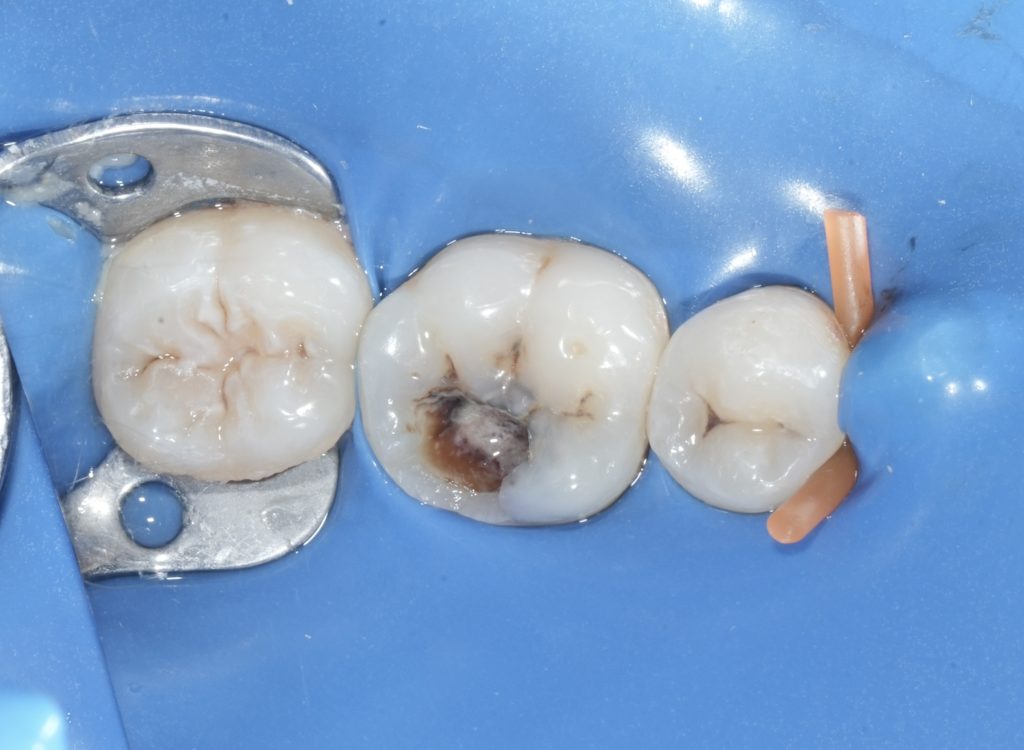

Case Assessment and Diagnosis

Clinical examination revealed a deeply carious mandibular first molar with pulpal involvement. Radiographic evaluation showed intact periapical structures and favorable root morphology. The tooth was deemed restorable with adequate remaining enamel and dentin, making it suitable for a bonded restorative approach following endodontic therapy.

Isolation and Access

Rubber dam isolation was established to eliminate salivary contamination and enhance procedural accuracy. Access cavity preparation was performed under magnification, prioritizing preservation of pericervical dentin. Canal orifices were located conservatively to maintain structural integrity.

Canal Negotiation and Shaping

Canals were negotiated and working length was established using radiographic verification. Shaping was carried out with a controlled, minimally invasive approach to maintain canal anatomy while allowing effective irrigation and disinfection.